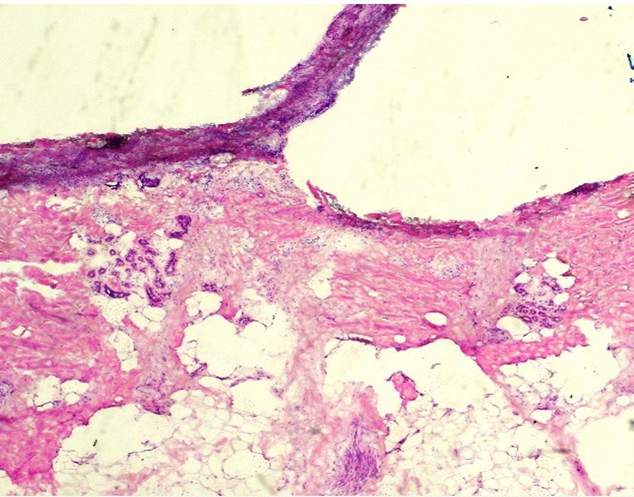

H E - Esquema de Mohs

Esta preparación teñida con H E muestra pliegues y arrugas, así como artefactos de congelación. Presenta agujeros y artefactos de recorte, y no se aprecia la epidermis completa. La intensidad de la hematoxilina es demasiado baja. Esta preparación obtuvo una puntuación de 4/10.